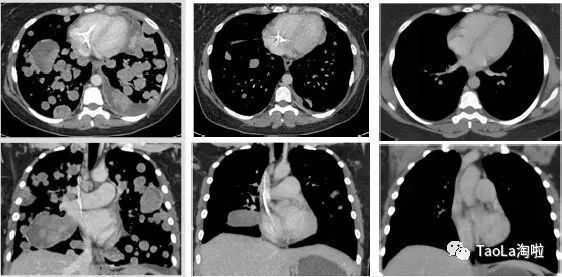

美国看病赴美就医治疗胃肠间质瘤:

55岁男性

治疗前:癌细胞几乎已经扩散到整个肠胃和腹腔

治疗后:接受了9个周期治疗后奇迹出现,肿瘤明显缩小,目前正在接受第10周期治疗。